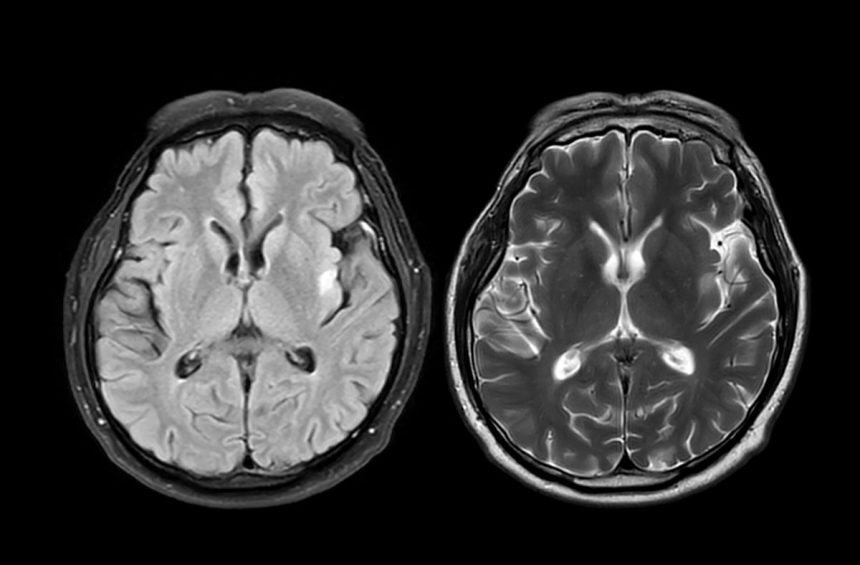

The study utilized data from the U.K. Biobank, a comprehensive health database that includes brain imaging from tens of thousands of participants. By training a machine-learning model to estimate “brain age” based on structural features seen in MRI scans, researchers were able to compare individuals who had scans before the pandemic with those who had scans before and during the pandemic. The results showed that brain aging accelerated in the group who experienced the pandemic, regardless of whether they contracted COVID-19.

Researchers in the U.K. analyzed brain scans from nearly 1,000 healthy adults both before and during the COVID-19 pandemic. The results were surprising: individuals living through the pandemic showed signs of accelerated brain aging, with their brains appearing about five and a half months older than expected based on pre-pandemic trends. This suggests that simply experiencing the stress and upheaval of the pandemic can have a measurable effect on brain health.